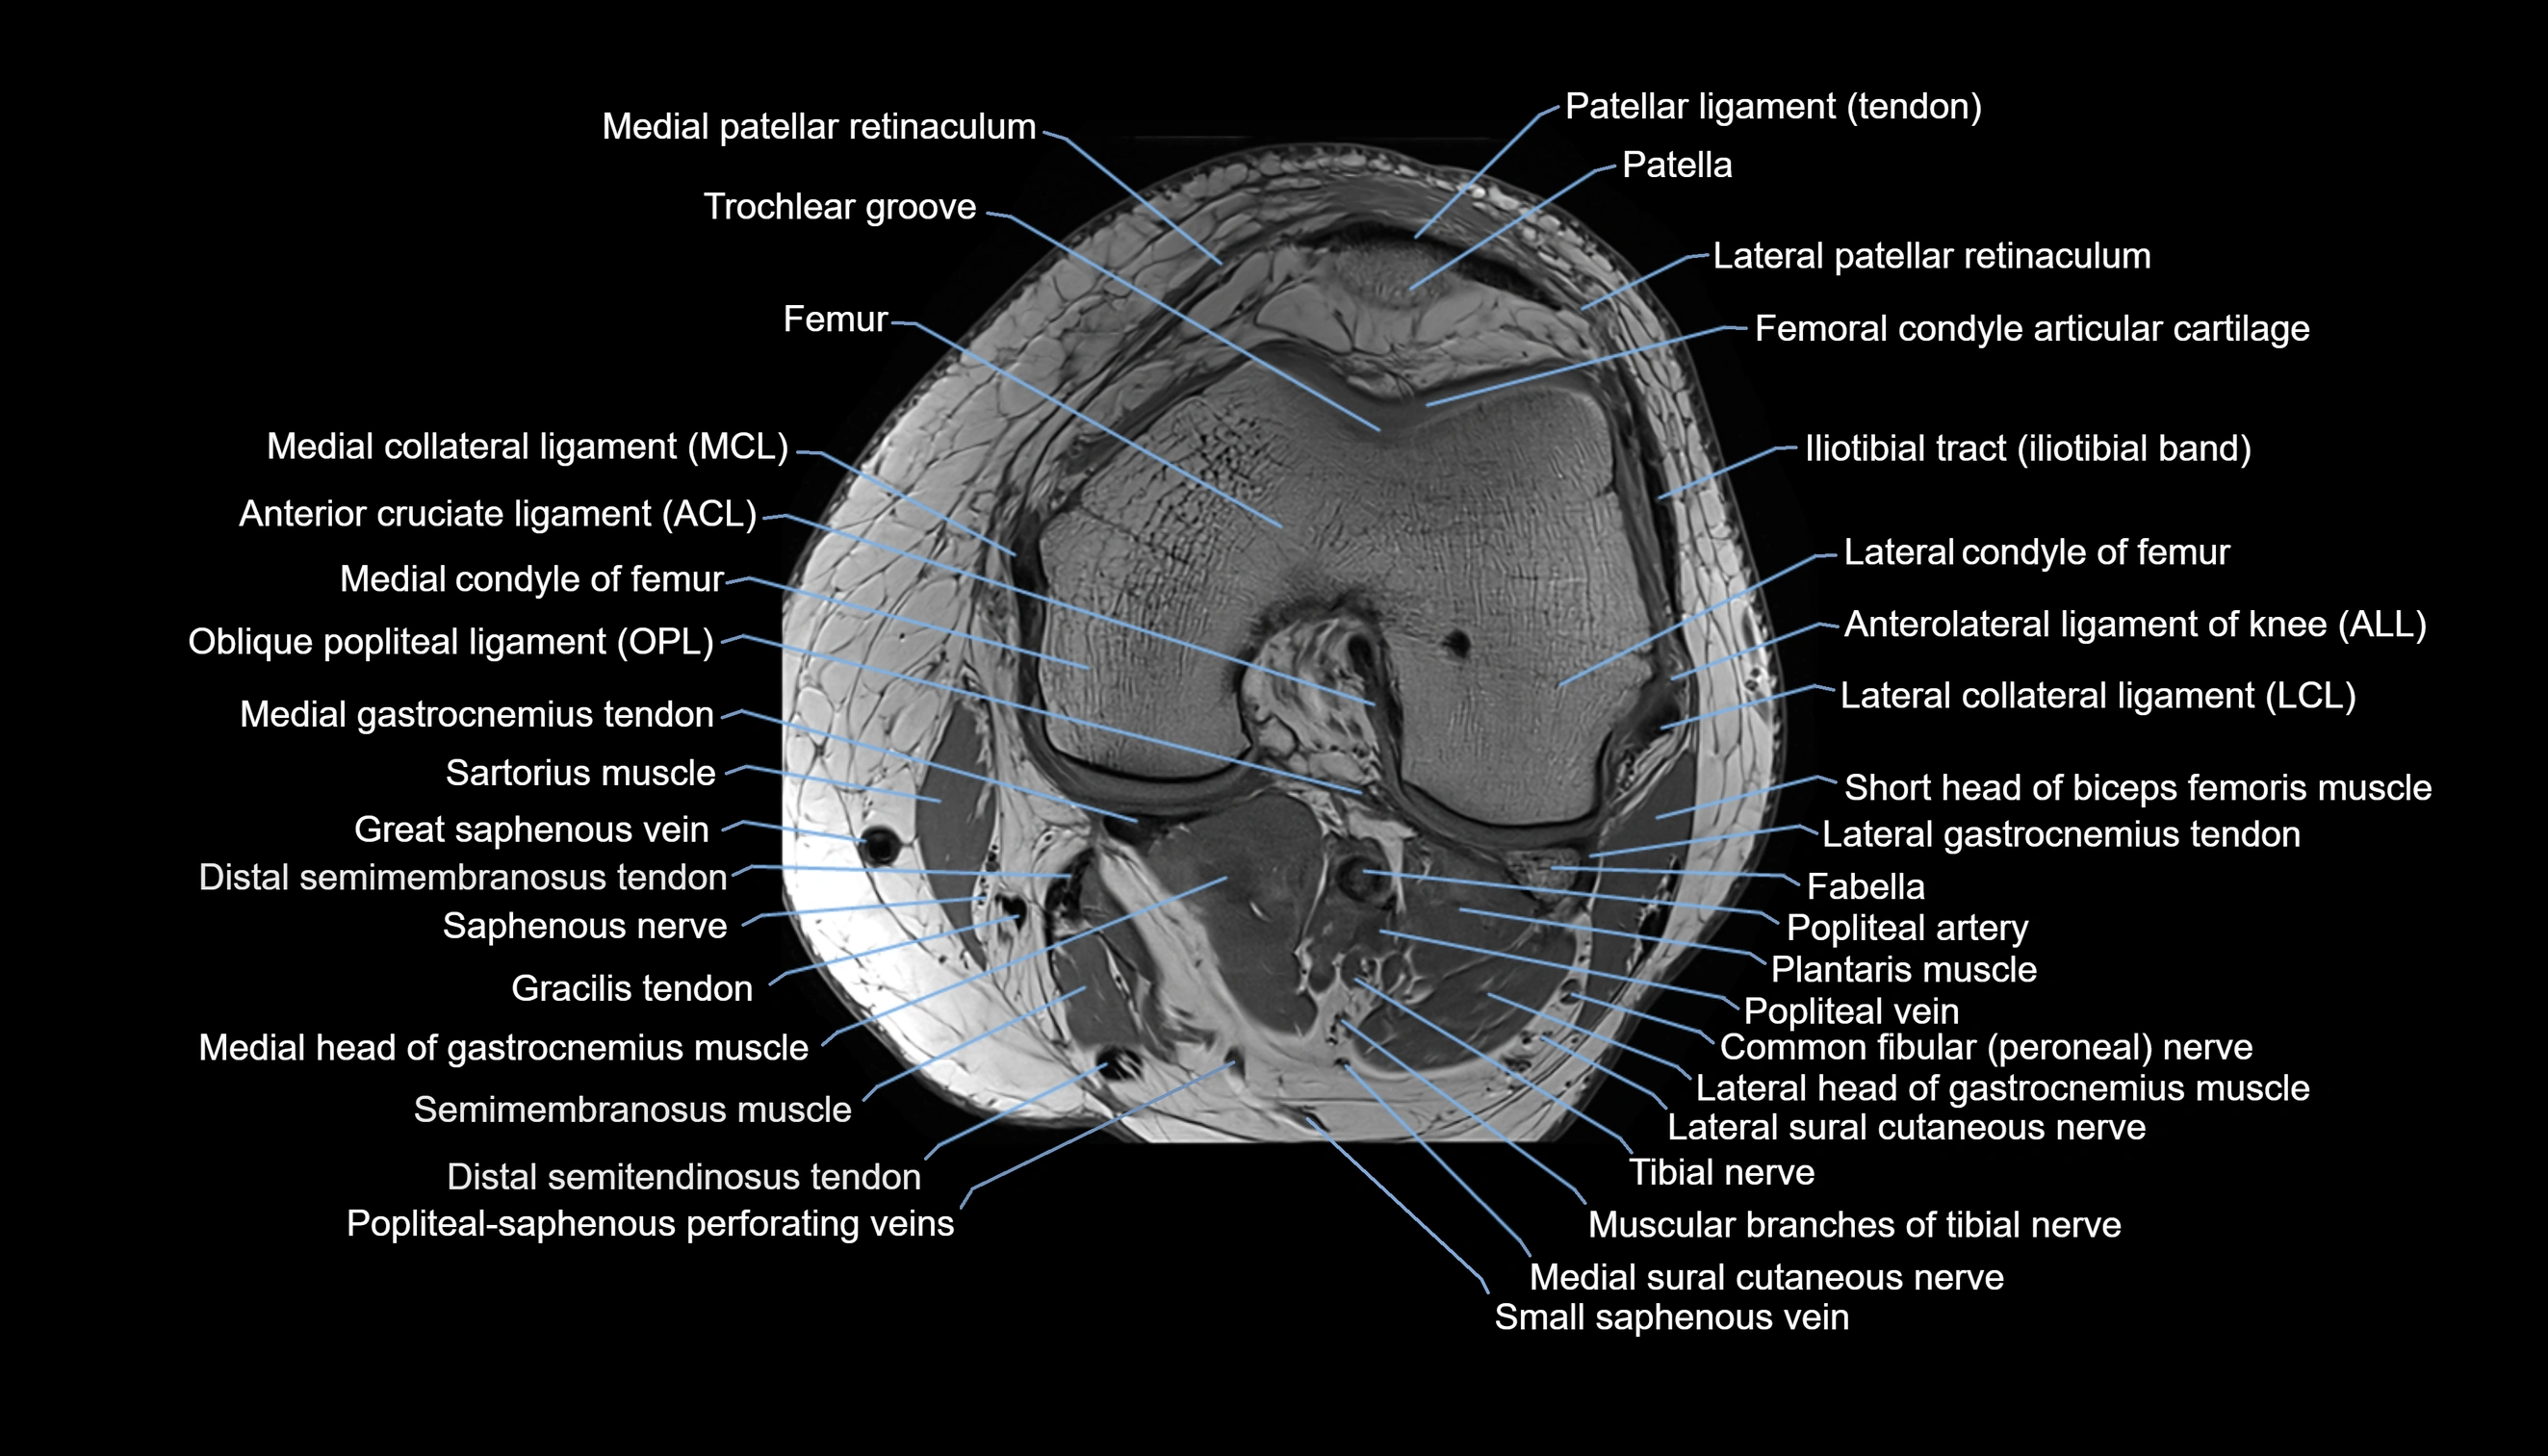

- Anterior cruciate ligament

- Anterolateral ligament of knee

- Femoral condyle articular cartilage

- Gracilis tendon (Distal)

- Infrapatellar branch of saphenous nerve

- Lateral collateral ligament

- Lateral condyle of femur

- Lateral gastrocnemius tendon

- Lateral head of gastrocnemius muscle

- Lateral patellar retinaculum

- Lateral patellofemoral ligament

- Lateral sural cutaneous nerve

- Medial collateral ligament

- Medial condyle of femur

- Medial gastrocnemius tendon

- Medial head of gastrocnemius muscle

- Medial patellar retinaculum

- Medial sural cutaneous nerve

- Muscular branches of tibial nerve

- Oblique popliteal ligament

- Patellar tendon (patellar ligament)

- Plantaris muscle

- Popliteal artery

- Popliteal lymph nodes

- Popliteal vein

- Popliteal–Saphenous perforating veins

- Sartorius muscle

- Semimembranosus muscle

- Small saphenous vein

- Tibial nerve

- Trochlear groove

- Vastus Lateralis Obliquus Muscle

- Vastus lateralis muscle

- great saphenous vein